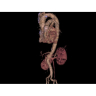

Компьютерный томограф GE Brivo CT385 представляет собой современное диагностическое оборудование, сочетающее высокую точность исследований с повышенным комфортом для пациентов. Этот аппарат открывает новые возможности для детальной визуализации анатомических структур.

Позволяет проводить комплексные исследования всех анатомических зон, включая нейровизуализацию, ангиографию, исследования органов грудной и брюшной полости. Особенно эффективен для раннего выявления онкологических заболеваний.